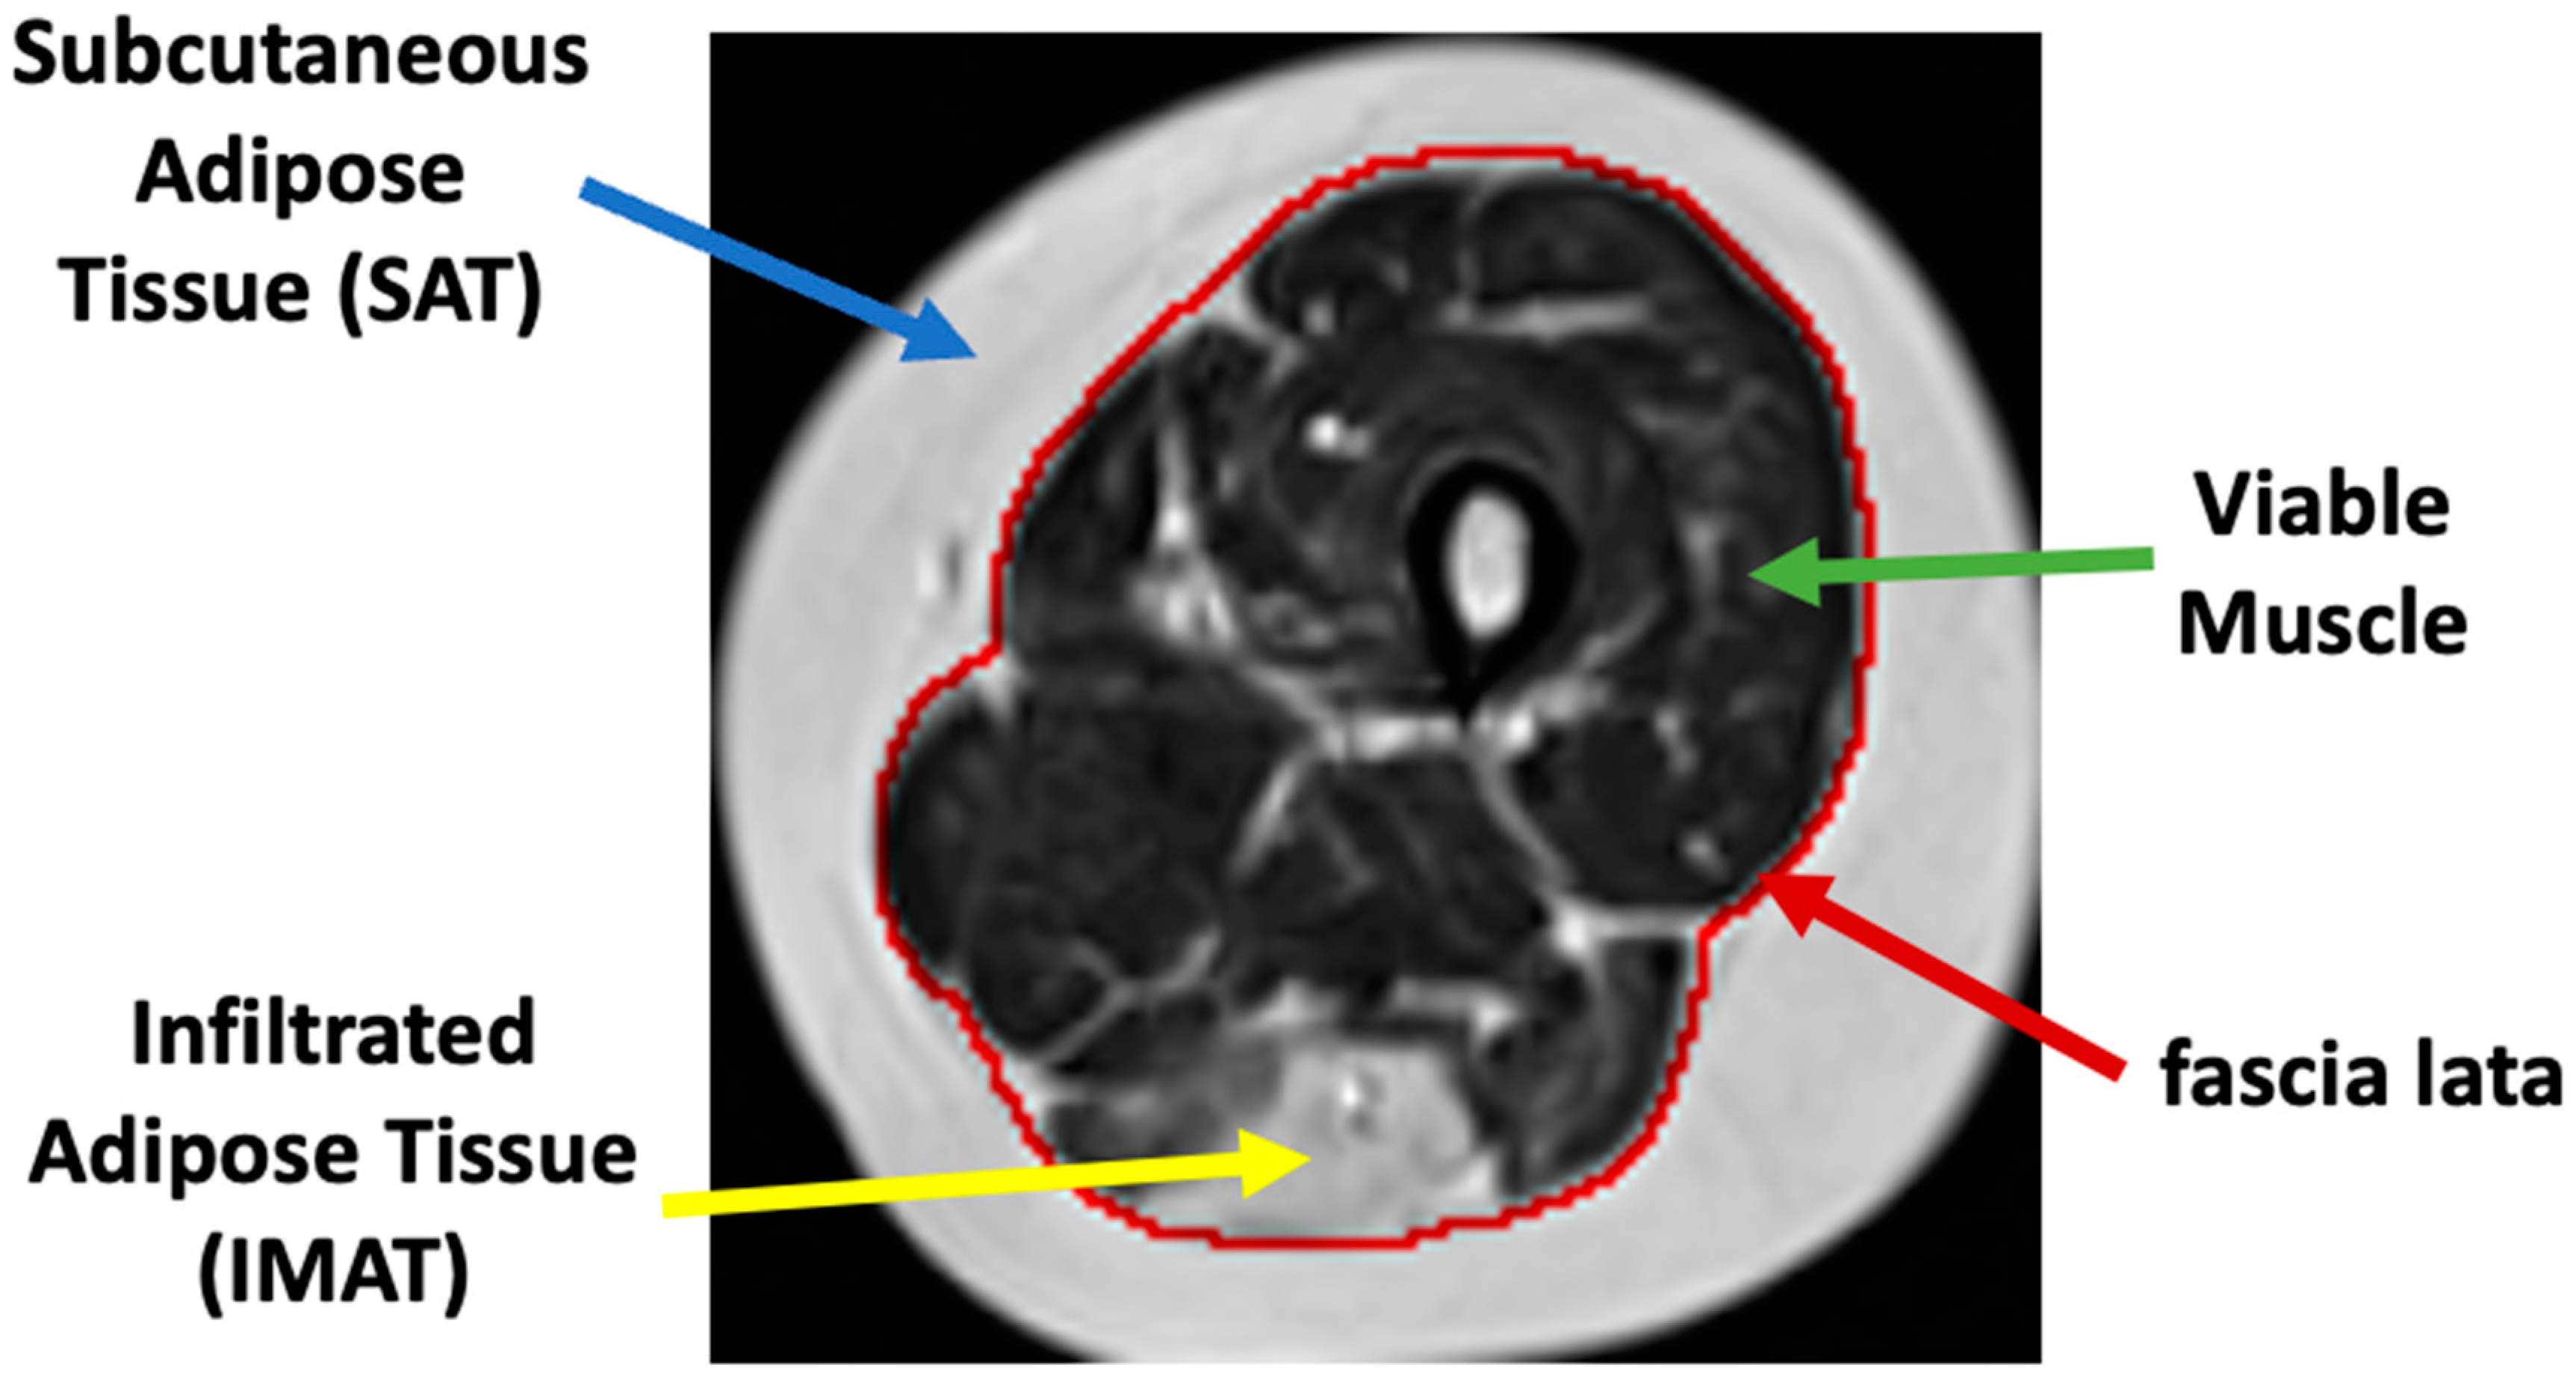

Muscle dystrophies (MDs) are an inherited class of disorders characterized by progressive muscle weakness that affects the upper and lower limbs, the axial muscles, and the facial muscles at variable levels of severity. Fat infiltration into muscles of the lower limbs is one of the hallmarks of these diseases’ progression and can be easily seen in MRI images. MDs lead to a loss of muscle mass and a weakening of muscle strength [1]. The infiltrated fat is usually referred to as intermuscular adipose tissue (IMAT) and is separated from the subcutaneous adipose tissue (SAT), which surrounds the muscle. The two fat tissues are separated by a boundary layer called “fascia lata”, used in many studies to achieve reliable segmentation of the lower limb anatomy (see Figure 1).

Figure 1. Axial MR image of the thigh. Red: fascia lata boundary; blue, green, and yellow arrows mark the subcutaneous fat, a region of viable muscle, and IMAT pixels.